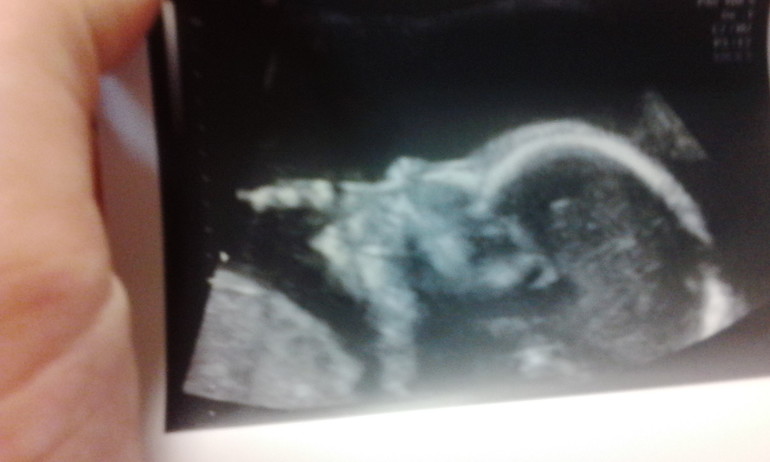

Вот грэческий профиль нашей дочи (абалдеть, до сих пор-то не верится, что 1 ребенок есть,а тут второй уже поспевает))